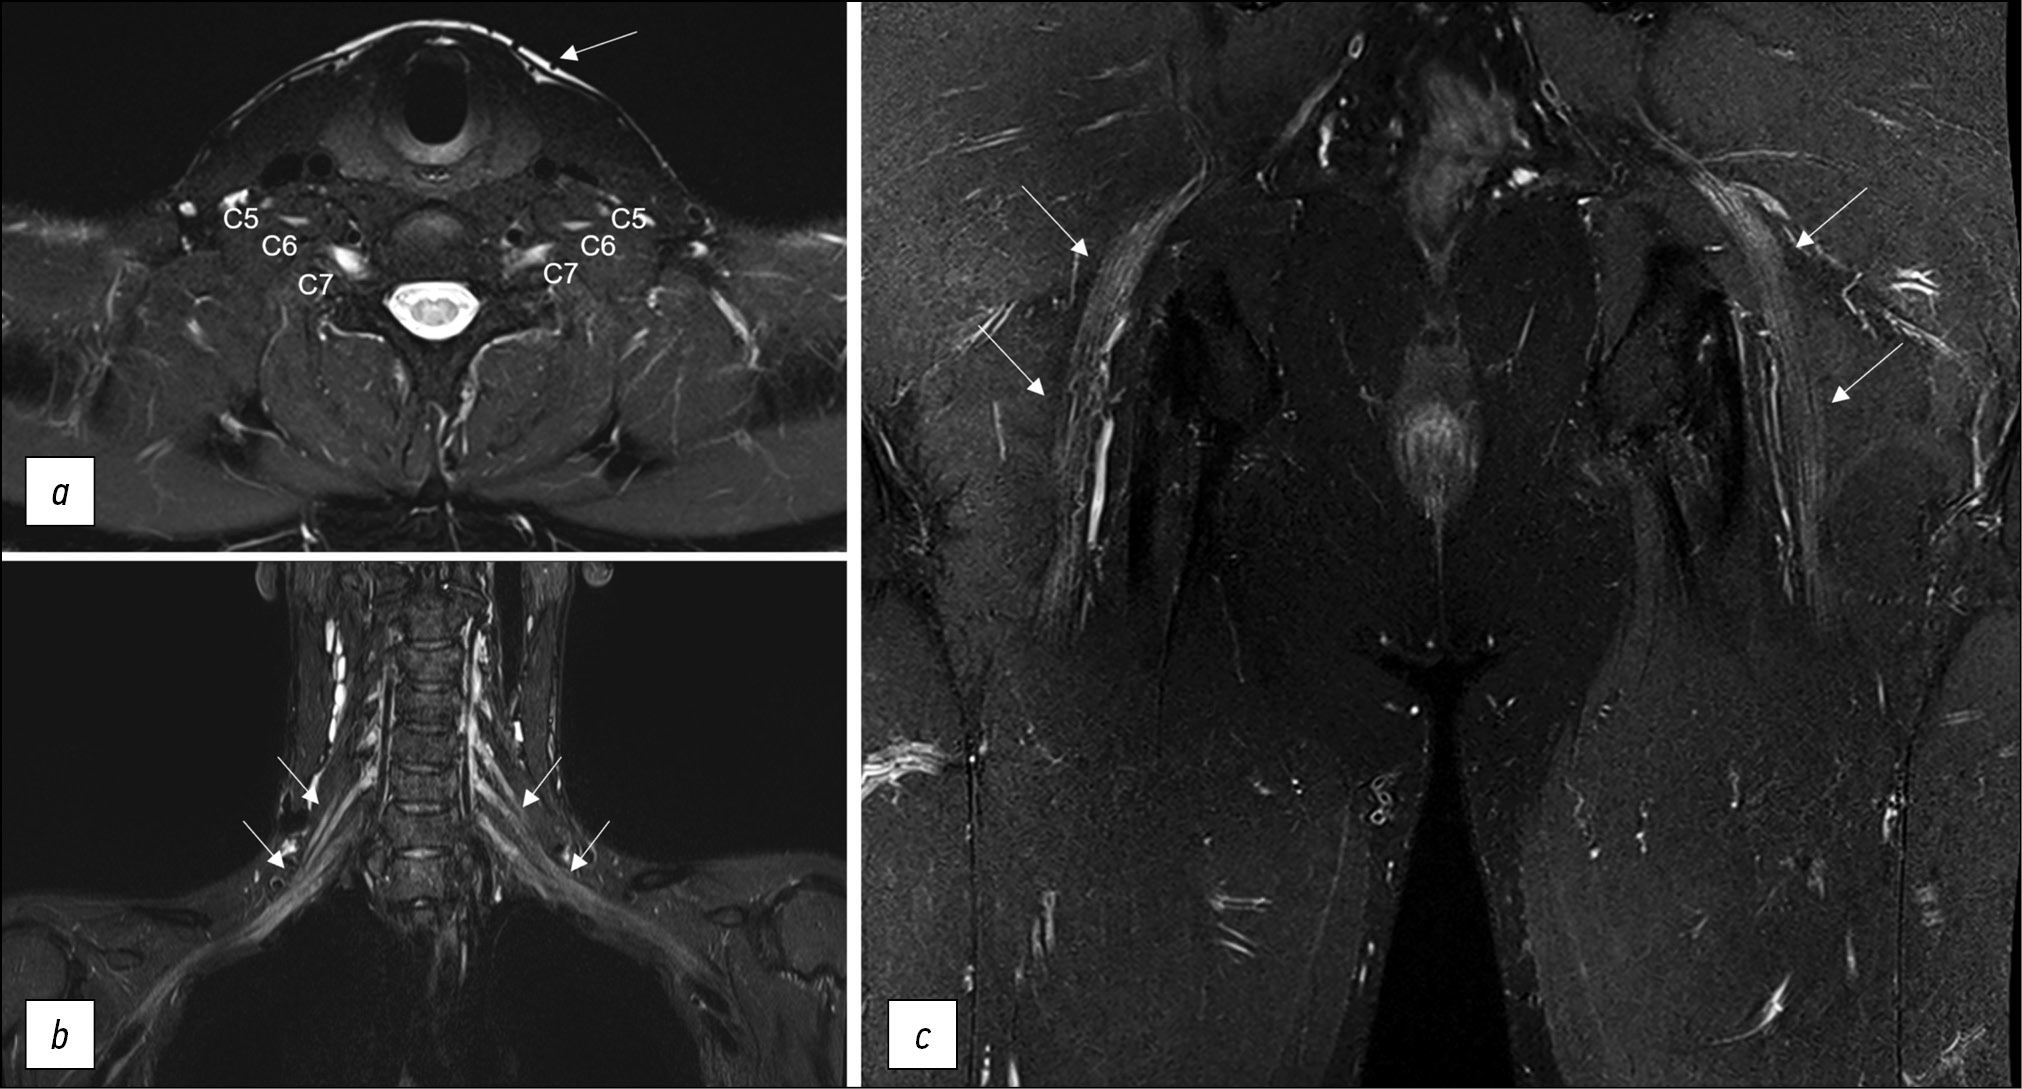

Fig. 3. Various techniques of fat suppression for magnetic resonance imaging: (a) brachial plexuses in T2-FatSat mode, an axial projection: the anterior branches of C5, C6, and C7 spinal nerves are noted, without abnormalities, with a slightly increased signal; heterogeneous fat suppression with unsatisfactory signal along the periphery of the area of interest (arrowed); (b) brachial plexuses in STIR mode, a coronal projection: homogenous fat suppression throughout the entire field of view, typical elements of brachial plexuses with a slightly increased signal (arrowed); and (c) sciatic nerves in T2-Dixon mode, a coronal projection: homogenous fat suppression, normal sciatic nerves with a slightly increased MR signal (arrowed).

The required fat suppression can be performed by spectrally selective fat suppression (FatSat) in T2-weighted spin echo sequences with high contrast, nearly no pulsation artifacts, and reduced magnetic susceptibility artifacts [33]. However, if there are metal structures in the field of vision, this technique should be avoided. The main disadvantage is poor fat suppression away from the center of the field of view or inhomogeneous fat suppression along the curves of the body [25].

Short-TI inversion recovery (STIR, where TI is the inversion time in milliseconds) provides excellent homogeneous fat suppression at various levels of magnetic induction and field homogeneity, but it is nonselective (it suppresses signal from all, not only fat, tissues with short T1). It cannot be used following intravenous contrast enhancement (as this sequence sums T2 and T1 contrast, providing only T2-weighted images). In many circumstances, it is susceptible to pulsation artifacts, erroneous nerve signal augmentation due to increased signal from intraneural fluid, and a low signal-to-noise ratio. Therefore, this sequence is more commonly used for plexus visualization, where spectrally selective fat suppression is ineffective for a variety of reasons, including the presence of metal in the field of view, using various modifications, such as shorter echo time (30–40 ms), a greater number of echo times, and a wider transmission frequency (400–500 Hz/Px).

T2 SPAIR (T2-weighted SPectral Attenuated Inversion Recovery), a combination of FatSat and STIR techniques, is the best sequence for extremity MR neurography because it suppresses fat signals similarly to STIR, but it is more selective in the center and periphery of the field of view with higher SNR and fewer pulsation artifacts. The signal from a normal nerve usually is isointense to the signal from skeletal muscle on T2-SPAIR images. Depending on the user’s preferences, weak and strong contrast types are available, with the weak giving higher signal homogeneity and the strong providing greater isointensity of the nerve signal. The main disadvantage of this sequence is the possibility of poor fat suppression in some edge slices, particularly along the scanning area’s boundary, and the inability to use this technique with low-field devices and significant magnetic field inhomogeneity. Although T2-SPAIR is less sensitive to metal artifacts than frequency-selective fat suppression sequences, the STIR sequence should still be used if the metal is in the scanning area.

The Dixon approach achieves optimal fat suppression, but image quality may be reduced from the central scanning area [25]. Thomas Dixon proposed this approach in 1984 [34]. The chemical shift effect was predicated on a difference in the resonance frequency of fat and water protons. A two-echo sequence is used. Water and fat signals occur in-phase and antiphase during the first and second echo times. Dixon demonstrated that additional images can be computationally created based on these images with simply the water signal (dixonW) and the fat signal (dixonF). The fat signal is suppressed in dixonW images. These images are commonly used in clinical practice because they provide homogeneous fat suppression, and the only notable artifact is a fat–water exchange caused by magnetic field inhomogeneity, which occurs frequently around the coil coverage area’s border [35]. However, due to the long scanning time, the use of this neurography technique is limited to 2D imaging.